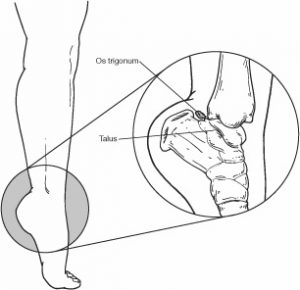

L’os trigonum è un ossiculo accessorio presenta a ridosso del comparto posteriore della caviglia, con variabili dimensioni.

Va distinto dallo pseudo os trigonum creato da un distacco del margine osteofitario posteriore dell’astragalo e quando crea un documentato conflitto posteriore nella caviglia può essere asportato in artroscopia

c) La sindrome da impingement posteriore, tipica dei danzatori e dei ginnasti, è di solito determinata dalla presenza di un os trigonum o da un tubercolo posteriore dell’astragalo prominente che determinano una reazione infiammatoria sinoviale a tale livello. Ci sono, comunque, altre cause ossee e dei tessuti molli, che giustificano il termine generico di impingement posteriore di caviglia. All’esame obiettivo si hanno dolore durante la flessione plantare passiva e dolorabilità alla palpazione della porzione posteriore della caviglia con possibile limitazione alla flessione plantare. Queste alterazioni sinoviali sono ben dimostrabili all’esame RM che mostra la distensione di queste strutture sinoviali, dovuta alla presenza di versamento, documentato da una tipica iperintensità di segnale nelle sequenze T2 pesate e ipointensità nelle sequenze T1 pesate; anche le cause di impingement sono dimostrate con questa tecnica .

Se osserviamo con attenzione il margine posteriore del corpo dell’astragalo, vediamo che questo presenta una sporgenza, detta tubercolo posteriore che, nella maggior parte delle persone, si unisce al resto del’osso tra i nove ed i dodici anni di età (Kadel et al., 2000): in una certa percentuale di persone, tuttavia, questo tubercolo resta separato dal resto dell’osso e prende il nome di os trigonum, a causa della sua forma vagamente triangolare; in altri soggetti, invece, quando il tubercolo posteriore dell’astragalo è particolarmente grande ed “ingombrante”, viene definito come processo di Stieda (Clippinger, 2007).

In presenza delle due condizioni sopra descritte, quando il danzatore forza il movimento di massima flessione plantare, la porzione posteriore della capsula articolare della caviglia ed i tessuti molli adiacenti possono essere bruscamente compressi contro il margine posteriore della tibia dando origine, appunto, ad una limitazione della mobilità articolare. Tale situazione si verifica soprattutto se, per stendere la punta, viene utilizzata prevalentemente la contrazione del muscolo tricipite surale: la brusca sollecitazione del tendine d’Achille, infatti, richiama troppo velocemente indietro il calcagno e l’astragalo si blocca all’interno della pinza mentre la presenza dell’os trigonum o del processo di Stieda comprime ulteriormente capsula e tendini posteriori.

La diagnosi si basa sull’esame obiettivo e sulla conferma della presenza di un os trigonum o di un processo di Stieda tramite una radiografia del piede in proiezione laterale; nella maggior parte dei casi altri tipi di accertamenti diagnostici non sono necessari. L’esperienza tuttavia mi obbliga a fare una considerazione: se si vuole avere la certezza di essere in presenza di una sindrome da “impingement” posteriore della caviglia, gli esami radiografici dovrebbero essere sempre visionati da personale sanitario esperto in “patologie da danza”.

I referti radiografici, infatti, solitamente non considerano patologiche le diverse forme dell’astragalo per cui descrivono come “normali” le varianti anatomiche legate alla presenza dell’os trigonum e del processo di Stieda: anche in presenza di un referto radiografico totalmente negativo, dunque, soltanto lo specialista che conosce il lavoro del piede del danzatore è in grado di poter fare una corretta diagnosi.